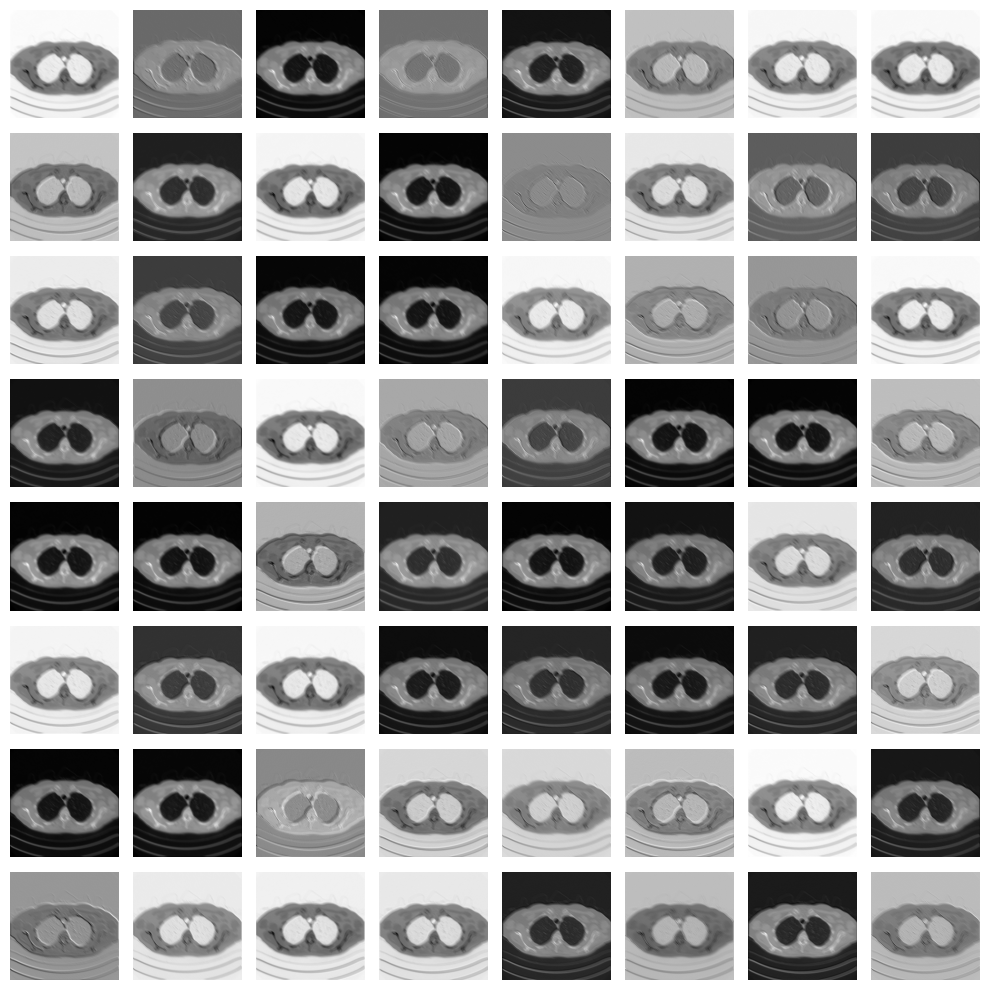

Given a trained CNN, we can also investigate what are e.g. the operation learnt on the first convolutional layer:

# Variable to store the output

conv1_output = activation['conv1']  # Shape: [1, 64, 256, 256]

# Plot all channels

fig, axes = plt.subplots(8, 8, figsize=(10, 10))

for i, ax in enumerate(axes.flat):

ax.imshow(conv1_output[0, i].cpu(), cmap='gray')

ax.axis('off')

plt.tight_layout()

plt.show()

../_images/c0733800514155b5aab30acfe2ac34cee85ac18cc7932b252bc99bcaa614b93a.png

As you can see, each convolutional layer visualizes a particular pattern of the input image, each of which is then processed again by the second convolutional layer to attempt to solve the image reconstruction task.